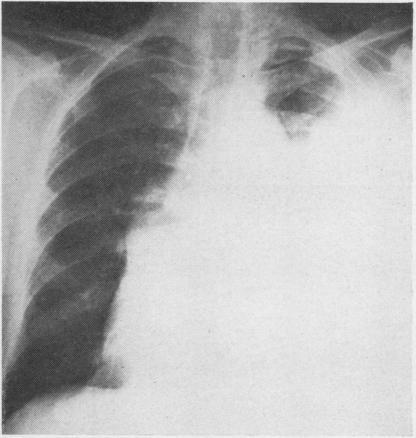

GINGELL J C

Thorax. 1965 May;20(3):261-9. doi: 10.1136/thx.20.3.261.